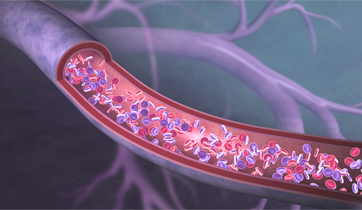

EnCompass F2 Device for cerebral embolic protection system in TAVR procedures

EnCompass Technologies

EnCompass’ F2 filter has pores small enough to block most emboli to the brain while preserving blood flow. During the TAVR procedure, 360-degree wall apposition of the filter in the aortic arch prevents migration. The filter, attached to a self-expanding, nitinol stent, is easy to insert, deploy and retrieve, according to the company. Copyright ©2021 KO Studios.